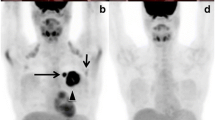

Figure 1 shows representative examples of FDG PET images obtained in study patients. The images in the upper frames illustrate a patient with decreasing FDG uptake after therapy. The patient’s initial FDG PET scan demonstrated a maximum SUV reading of 5.2 at the index lesion located in the lumbar spine at the level of L4. Following treatment, the SUV reading decreased to background levels of 2.2. The images in the lower frames of Fig. 1 illustrate an increase in FDG uptake with treatment. Table 2 summarizes initial maximum SUV values and FDG PET changes for the cohort. The average pre-treatment SUV was 5.9. The average SUV change during treatment was a decrease of 2.2, ranging from a decrease of 9.2 to an increase of 2.8. The average percentage change in FDG PET was a 33% decrease in SUV.

Serial FDG PET imaging examples. The upper frames illustrate representative coronal images from serial FDG PET scans on a patient with decreasing FDG uptake after therapy. The index lesion in the lumbar spine at L4 demonstrates a SUV of 5.2 on the initial scan (upper left). Following treatment, the SUV reading of the L4 lesion decreased to background levels of 2.2 (upper right). The lower frames depict coronal images from a patient with increased FDG uptake after therapy. The index lesion in the thoracic spine increased from an initial SUV of 3.4 (lower left) to a post-therapy SUV of 8.0 (lower right)